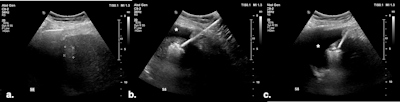

(A) Targeted HCC in segment VIII. (B) Microwave ablation in progress, with artificial ascites (*) separating the liver from the diaphragm. (C) Oblique image compared with the previous one, showing further liver displacement from the diaphragm through mechanical leveraging and illustrating continuous monitoring of the ablation zone. All figures courtesy of Dr. Bruno Di Muzio and Department of Radiology, Alfred Health, Melbourne, and presented at RANZCR's 2024 ASM.

This procedure uses a microwave antenna to displace the liver away from at-risk structures, usually in combination with artificial ascites, enhancing the protection of adjacent viscera against thermal injury. It can be useful in patients with adhesions.

"Mechanical displacement technique involves tilting the microwave needle handle to shift the liver away, thereby creating a wider gap between the ablation zone and organs at risk of collateral thermal injury," the authors stated. "When treating cirrhotic livers, which are typically stiff and smaller in volume, leveraging techniques can achieve significant displacement."